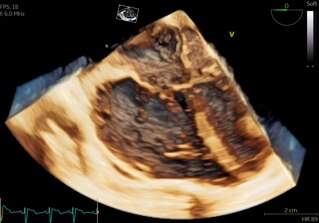

9VT-D gives you access to real-time multiplane and 4D imaging to help improve diagnostic and procedural confidence in patients as small as 5 Kg. Get clear and realistic visualizations of pediatric heart structures with 4D color flow analysis.

The 9VT-D probe’s revolutionary 4D imaging capabilities offer clearer views of the heart, enhancing both pre-surgical planning and real-time guidance during complex pediatric interventional procedures.